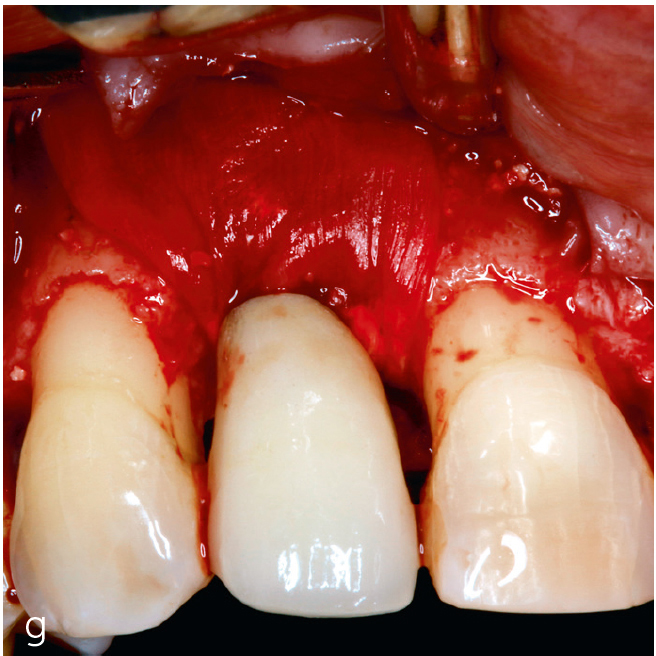

Die kombinierte chirurgische Periimplantitstherapie ist bei fortgeschrittenen Knochendefekten mit komplexer Morphologie indiziert64 (Abb. 3). Die Kombination augmentativer Verfahren mit der Implantoplastik, die am suprakrestalen Implantatanteil vorgenommen wird, zeigt nach einem Beobachtungszeitraum von 7 Jahren eine hohe Effektivität48,65.

Abb. 3a bis h Falldokumentation mit Zustand nach Implantation und lateraler Augmentation alio loco: a) klinische Ausgangssituation mit Fistelung vestibulär in der Region 12; b) klinische Parameter (PI=Plaque Index 1-3, ST=Sondierungstiefe, MR=Mukosarezession, KM=keratinisierte Mukosa, BOP=Bleeding on probing, SUPP=Suppuration); c) radiologische Ausgangssituation mit initialem periimplantären Knochenabbau; d) operativer Zugang; e) Defektdarstellung nach Entfernung des periimplantären Entzündungsgewebes; f) Defektaugmentation mit einem Gemisch aus Eigenknochen und xenogenem Knochenersatzmaterial; g) Kollagenmembran; h) das aus dem Gaumenbereich entnommene Bindegewebstransplantat (BGT).